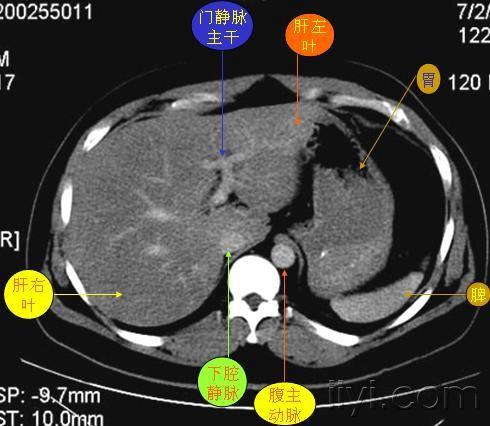

分享一个腹部ct解剖,希望能对大家有帮助

每位影像科医生都应该掌握的腹部ct基础读片36张看完就会了